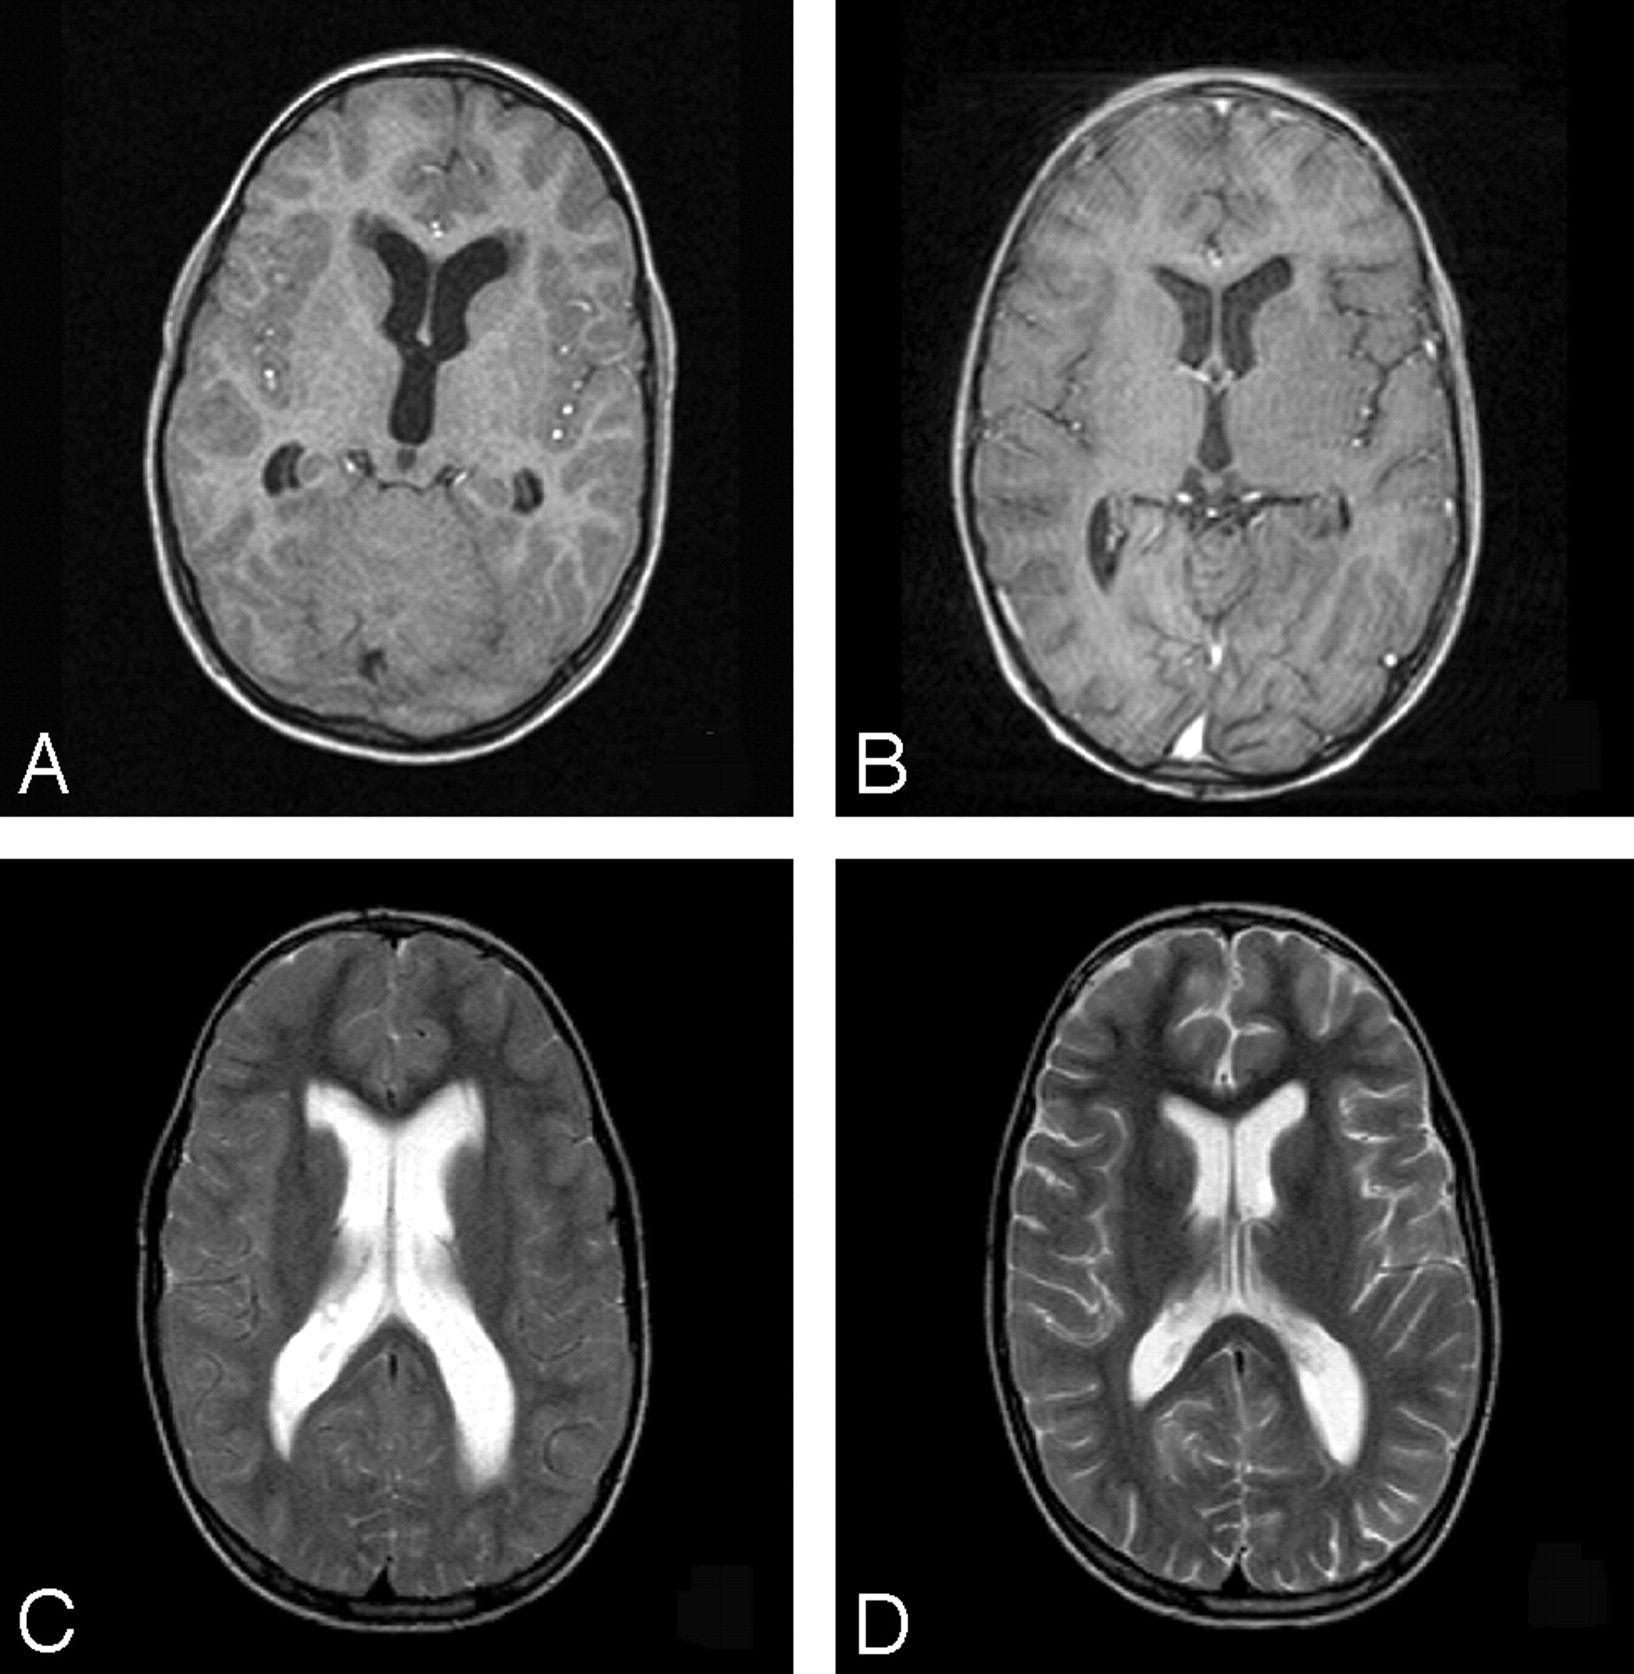

A second explanation for the observed differences in MTR between DWMH and PVWMH is not based on differences in vascularization between these brain areas but on differences in interstitial fluid dynamics. Because the brain is devoid of a lymphatic system, interstitial fluid is transported through the extracellular space of the brain and through the ependymal lining to the ventricles.22,23 Once the CSF is in the ventricles, the ependymal lining prevents the it from leaking into brain parenchyma. Because in elderly subjects with PVWMH, partial disappearance of the ependymal lining of the ventricles has been observed, it is conceivable that increased interstitial water resulting from ependymal discontinuation contributes to the high signal intensity on T2-weighted MR images.10 The similarity between the distribution of age-related PVWMH and the reversible periventricular high signal intensity on T2-weighted images that can be observed in patients with obstructive hydrocephalus (Fig 5) supports this hypothesis. The observed lower MTR values in PVWMH compared with DWMH could thus be based on the additional contribution of increased interstitial fluid concentration on MTR values in the periventricular white matter, which is absent in the deep white matter.

Subject (8-year-old) with an obstructive hydrocephalus secondary to infratentorial mass before (A, T1-weighted image; C, T2-weighted image) and after placement of a ventriculoperitoneal shunt (B, T1-weighted image; D, T2-weighted image). Notice the location and lining of the areas with increased signal intensity hypointensities on T1-weighted images in the periventricular white matter before drainage (A), disappearing after drainage (B).